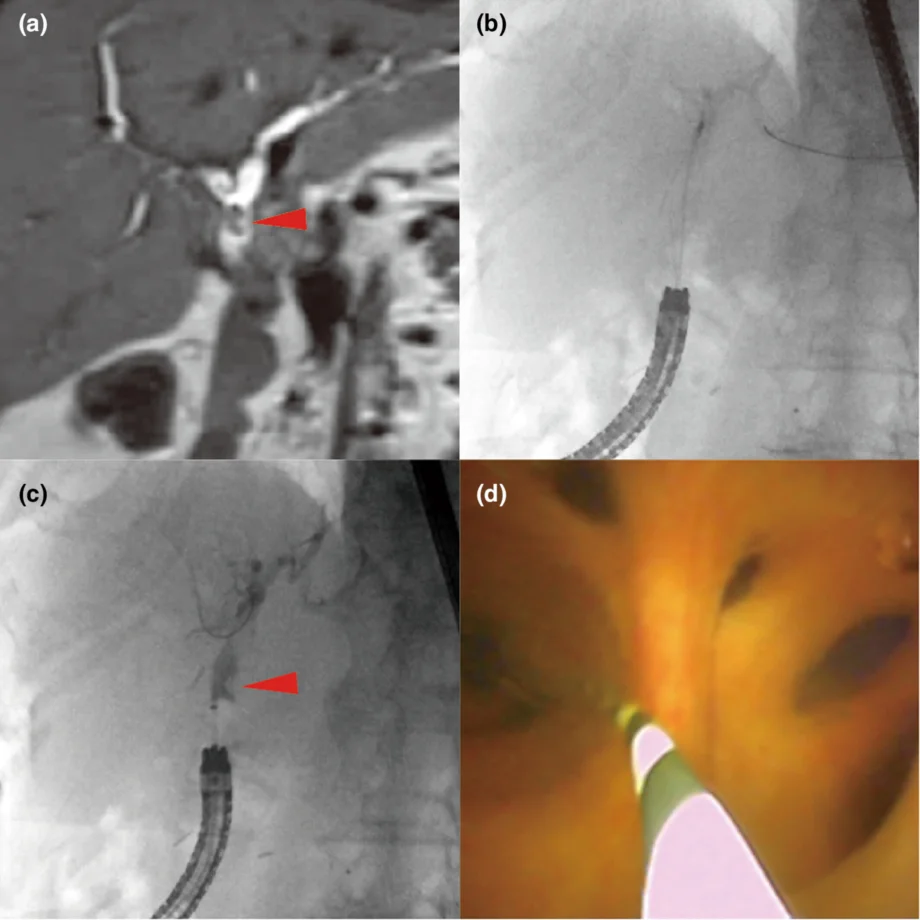

Low-cost and reliable method for confirming residual bile duct stones utilizing a novel peroral cholangioscope

Shun Ishido, Masanori Kobayashi, Ryuichi Okamoto

DEN photo